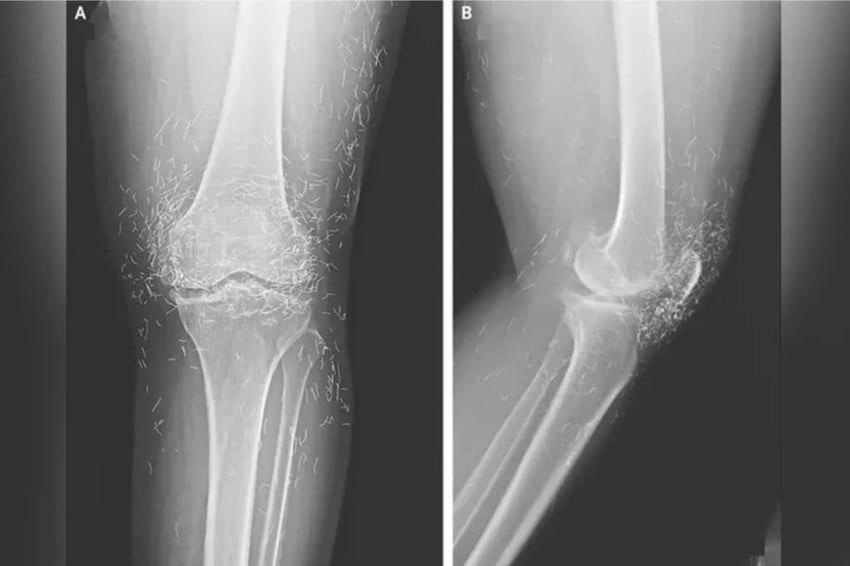

Viral! Dokter Temukan Ratusan Benang Emas Murni di Lutut Wanita Ini

loading… Sebuah peristiwa medis yang mengejutkan terjadi di Korea Selatan ketika tim dokter menemukan ratusan